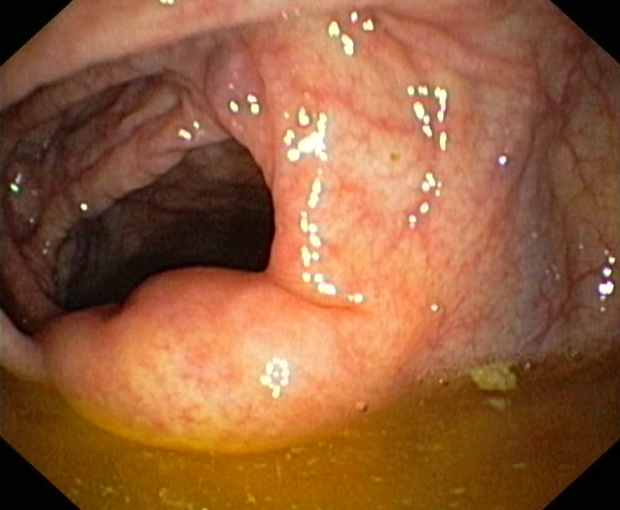

Ileocaecal valve